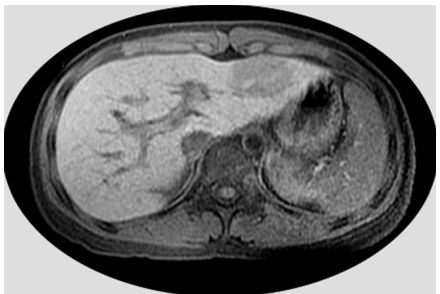

75.5歲男童因超音波篩檢發現腹部腫瘤,磁振造影T1加權影像如圖示,則該腫瘤位於何處? (A)肝臟左外節 (B)肝臟左內節 (C)肝臟右前節 (D)脾臟內